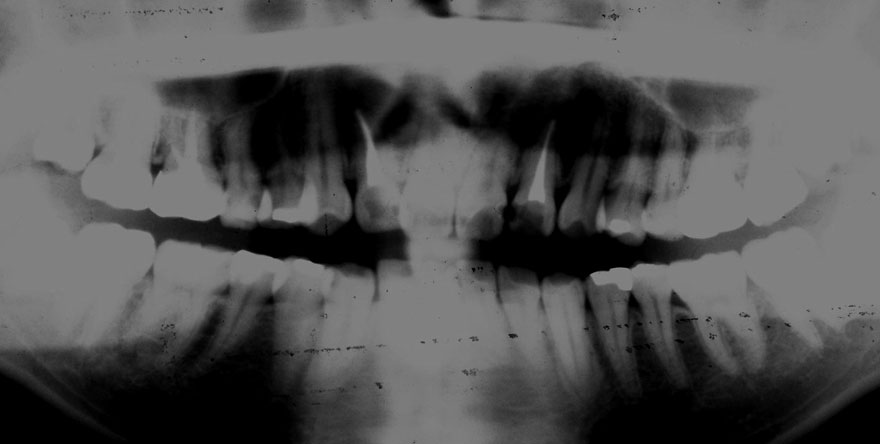

初診時 29歳 男性 平均歯槽骨喪失量:2.44mm

河田歯科医院

22年後 51歳

平均歯槽骨喪失量:2.21mm

22年間増量:+0.23mm

年間再生速度:+0.01mm

(ケア頻度:1.02ヵ月ごと)

初診時 29歳 男性 平均歯槽骨喪失量:1.88mm

20年後 49歳

平均歯槽骨喪失量:2.34mm

20年間喪失量:-0.46mm

年間喪失速度:-0.02mm

(ケア頻度:2.65ヵ月ごと)